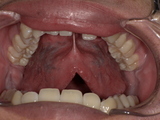

6. 症例紹介:滑舌が改善した20代男性のケース

● ご相談内容

ラ行・サ行の発音が不明瞭で、職場での会話にも影響していた20代男性。

診察の結果、舌小帯が短く、舌先が上あごに届かない状態でした。

● 治療内容

Before

舌小帯が短く、舌先を上あごまで十分に持ち上げることができません。